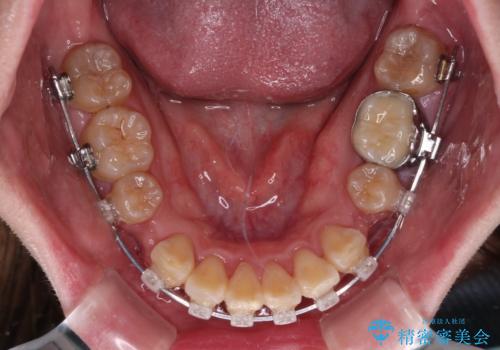

- クリアブラケット

- 2年4ヶ月

口元を積極的に引っ込めるために、上下左右の小臼歯計4本を抜歯することとしました。

4本の歯を抜歯したことで、飛び出していた口元が引っ込み、横顔が大きく改善されました。